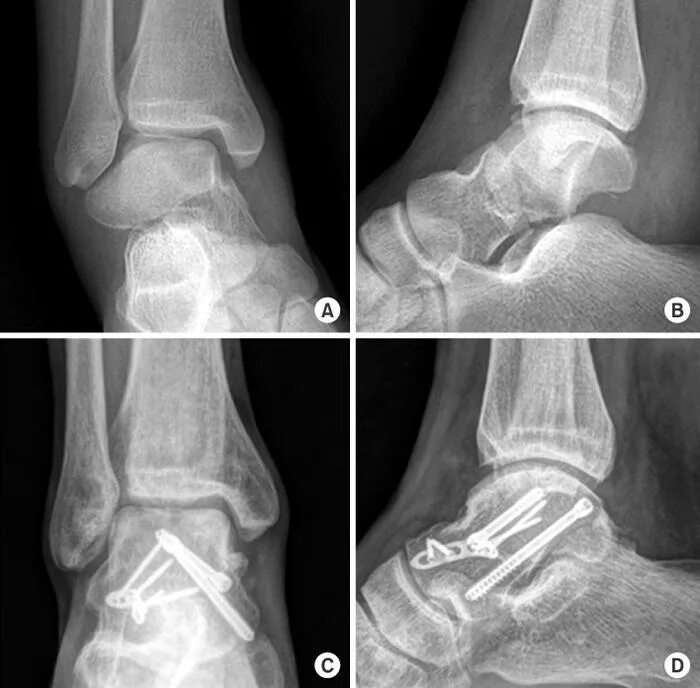

Перелом задней кости стопы